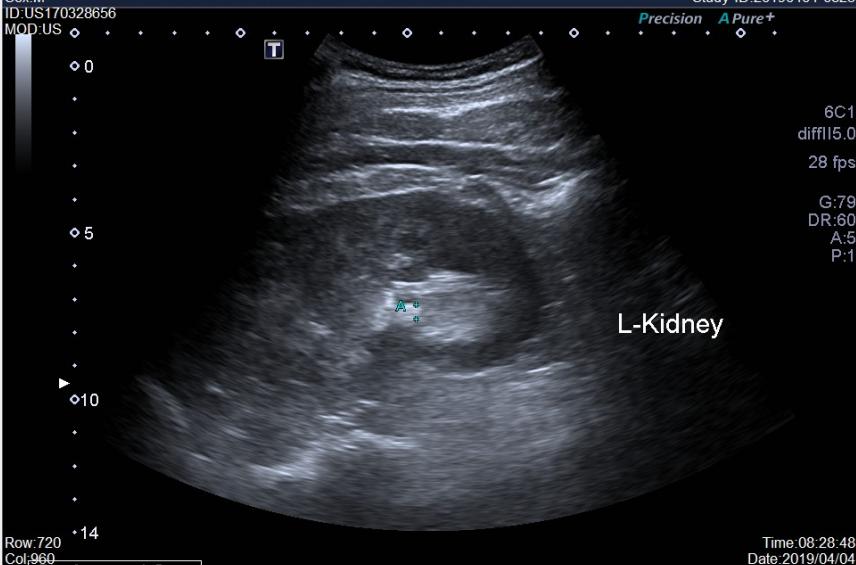

肾结石的B超

我们举一些临床常见的尿常规异常情况和疾病的关系。如泌尿系统肿瘤、结石、结核、外伤或者血液系统疾病等均可出现血尿,尿液发红,尿中高倍镜下红细胞数量增多;泌尿系感染如急性肾盂肾炎、膀胱炎等可出现尿高倍镜下白细胞数量增多,甚至出现脓细胞;尿比重增加,提示肾脏疾病或者体内水分丢失过多等等;尿比重下降,提示出现尿崩症以及各种原因引起的慢性肾病等疾病;糖尿病患者会出现尿糖;糖尿病酮症会出现尿酮体;急性胰腺炎患者,不仅仅血淀粉酶会升高,尿淀粉酶也会升高;有黄疸或者肝病,会出现尿胆原、尿胆红素增加;肾病综合征及流行性出血热等肾脏的原发或者继发性疾病会出现大量的尿蛋白……